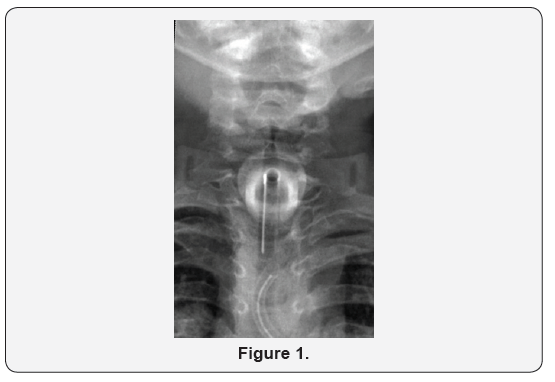

A 3 year old girl had a history of Down syndrome and bilateral choanal atresia with recurrent restenosis. She had undergone tracheostomy at age 3 months. She presented to the ENT emergency department in Sabah hospital with a history of t-tube separation from the flange during routine suctioning at home. When changing the t-tube, her mother noticed that the old tube was missing and immediately took her to our hospital. Prior to presentation, the patient had experienced a brief cyanotic attack. On presentation, she was distressed, with an oxygen saturation of 99% in room air. Her heart rate was 155 bpm, and her temperature was 36.10C. On auscultation, there were equal bilateral air entry and secretion sounds. Anterior, posterior, and lateral neck X-rays revealed a separated t-tube within the trachea (Figures 1 & 2). The patient was immediately taken to the operating room, and she underwent diagnostic fiber optic bronchoscopy. A portion of the t-tube was revealed within the trachea, near the carina. The dislodged t-tube, which had inner and outer diameters of 3 and 4.2 mm, respectively, was extracted from the left main bronchus with a rigid bronchoscope (size 3.7 mm) (Figure 3). Finally, the t-tube was changed. After recovery, the patient was transferred to the pediatric intensive care unit for close observation. A repeat chest X-ray revealed normal findings. The next day, she was transferred to the general ward and was doing well. Her vital signs were normal, and oxygen saturation was found to be 98% in room air.